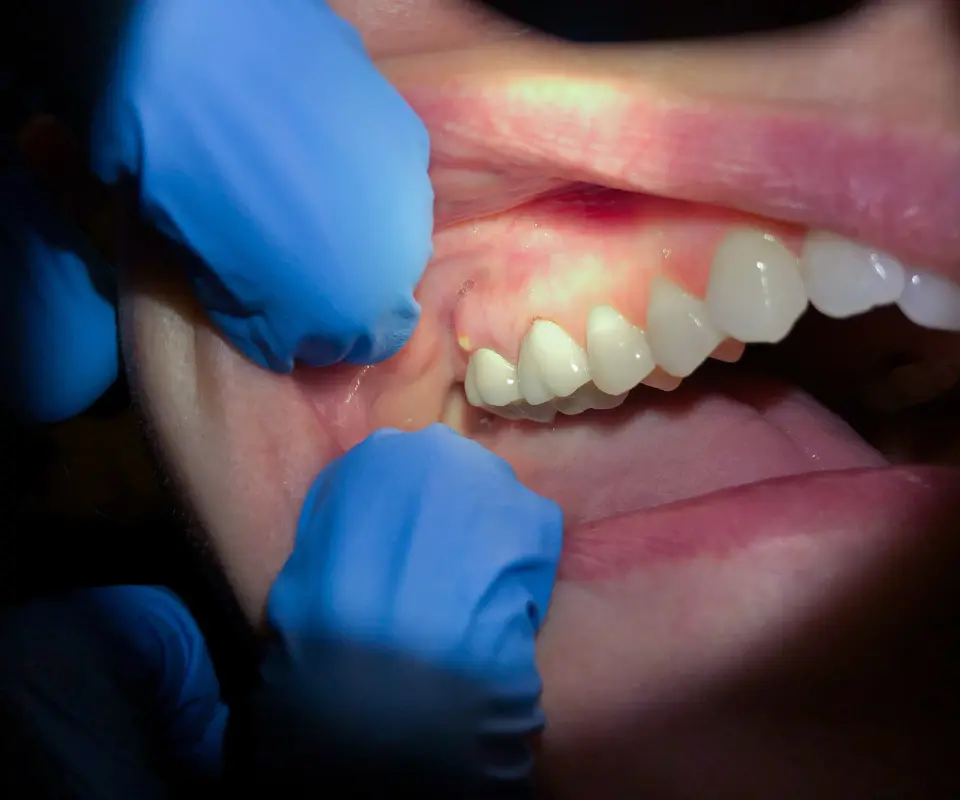

Swollen-Jaw-Relief-Tucker-GA